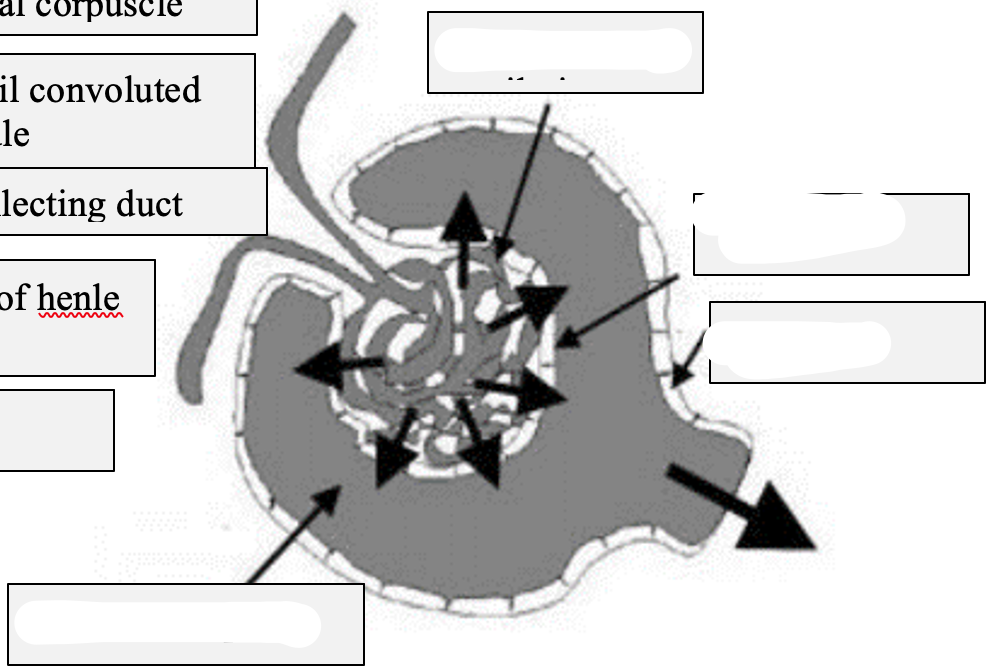

Label this diagram

Renal corpuscle

Glomeruli have a side next to blood vessels- vascular side

And then one going into nephron- urinary side